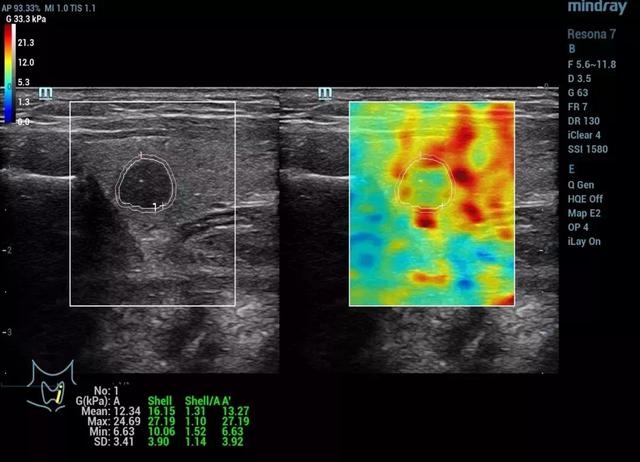

大会期间,深圳人民医院超声科董发进博士分享了基于迈瑞Resona 7的多模态弹性成像技术关于甲状腺癌诊断的最新研究报告。迈瑞的剪切波弹性成像提供了应变弹性和剪切波弹性成像的多模态弹性技术进行组织硬度的测量,其弹性比(Elastic Ratio, EI)和剪切模量(shear module, G)可以用于进行定量分析。研究报告的目的是应用全新可量化的剪切波弹性比和剪切模量进行甲状腺恶性结节的评估。

研究结果显示,恶性甲状腺结节的平均弹性比明显低于良性结节。(P<0.001)敏感度和特异性分别达到71%和73%。恶性甲状腺结节的剪切模量最大值,平均值和标准差明显高于良性结节。(P<0.005)。在剪切模量最大值的参考值(cut-off value)设置在15.82kPa的条件,能获得最高的AUROC值(0.84),敏感度和特异性分别达到79.17%和79.03%。研究结果表明,可量化的剪切波弹性技术将会是一个新的辅助诊断甲状腺结节良恶性的超声工具之一。

甲状腺乳头状癌病例(2)